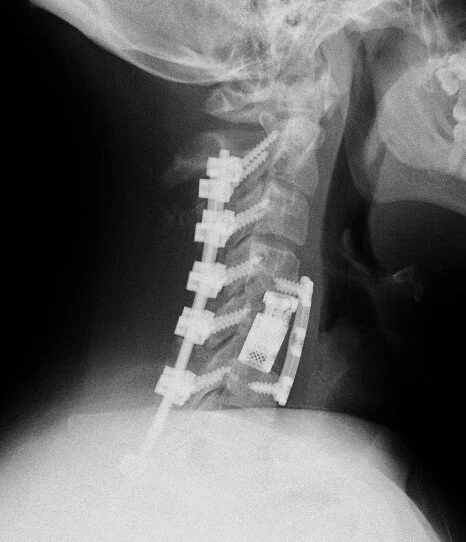

Cervical Spine Revision Surgery

Revision of a cervical spine surgery can be needed for a variety of reasons: failure for bones to fuse (cervical pseudoarthrosis), malposition or failure of implanted hardware, inadequate decompression of the spinal cord or nerve roots, new or persistent neck pain or cervical radiculopathy or myelopathy symptoms, degeneration of neighboring spinal segments, infection, spinal instability, and others.

Management options for a failed cervical surgery might include ACDF, cervical corpectomy, CORUS cervical fusion, or posterior cervical fusion, among others. Each of these options has benefits and drawbacks. The right surgery for you will depend on your symptoms, your previous surgery, the number of spinal levels affected, and factors related to your medical history, age, smoking status, and spinal anatomy.